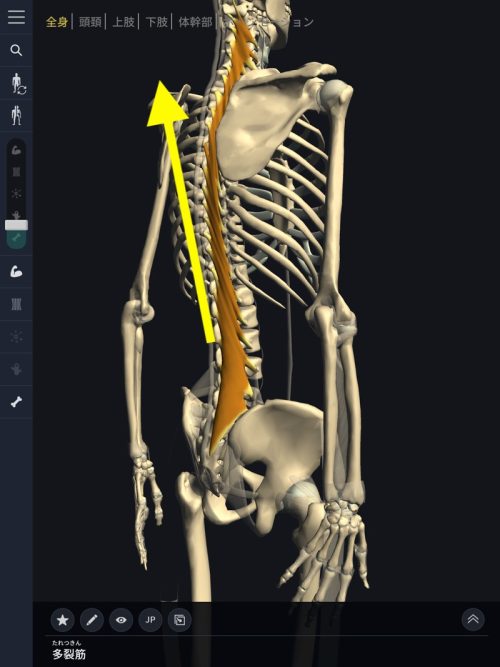

そしてもう1つ。腰椎(腰骨)の同じ部分に多裂筋という背骨に沿った筋肉も付着しています。

多裂筋

起始:仙骨背面、後仙腸靱帯、腰椎の乳様突起、胸椎の横突起、C4-7の頚椎関節突起

停止:2-4個上の椎骨の棘突起

働き:腰部の伸展運動・同側への側屈運動・対側への体幹回旋運動

この多裂筋は首コリや肩こりの酷い方は硬直している場合が多く、デスクワークの方には顕著に硬直が見られます。

多裂筋に硬直により上と下に引っ張り合う

硬直した筋肉は固くなり縮む習性がありますので、多裂筋の硬直により背中が凝る(固まる)または上方向に腰椎を引っ張る状態が発生します。

この状態で大腰筋が硬直すると大腰筋が腰椎の付着部分を下方向へ引っ張るので多裂筋と上と引っ張りっこになり間の椎間板が耐えられず飛び出してヘルニアになるのです。